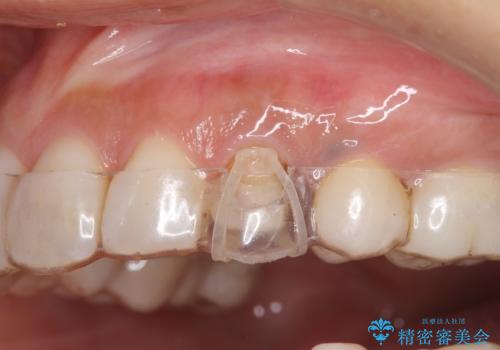

開始前

治療途中

左:虫歯を除去したところ。遠心が歯ぐきより深い状態です。中:そのままかぶせようとすると、遠心が歯ぐきが腫れやすい状態です。右:エクストリュージョンをしたことで、遠心の歯ぐきの腫れが収まっていることがわかります。